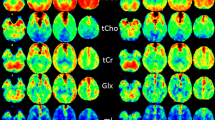

a Locations of each selected region of interest in the right brain hemisphere displayed as white filled circles on T2-weighted images of a 21-year-old healthy volunteer. The numbering represents the ROIs in the hand motor cortical area (1), postcentral gyrus (2), cingulate gyrus (3), splenium of the corpus callosum (4), thalamus (5), occipital area (6), temporal lobe lateral (7), temporal lobe medial (8), insular gyrus (9), hippocampus (10), cerebellum anterior lobe (11) and cerebellum posterior lobe (12). b Example metabolite maps of NAA, Cho, tCr, Glx, mI and spectral linewidth at the section level of the posterior cingulate gyrus with an example MR spectrum derived from wbMRSI. c Example tissue parameter maps of T2’, T1 and T2 at the section level of the posterior cingulate gyrus

Figure 1 shows the locations of selected regions of interest (ROI) in the right brain hemisphere, displayed as white filled circles or oval on the T2-weighted images of a 21-year-old female volunteer (Fig. 1a), the example tissue parameter maps and the metabolite maps at the section level of selected posterior cingulate gyrus ROI (Fig. 1b, c).